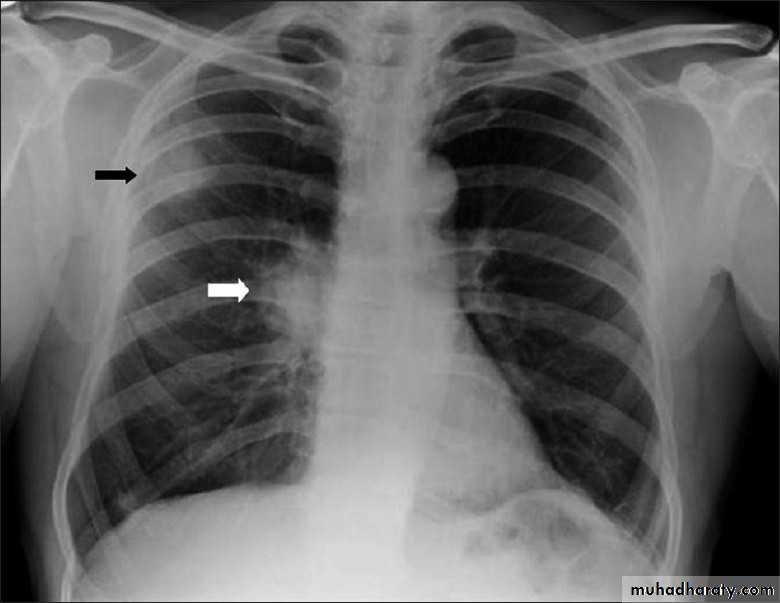

Golden S sign collapse with RT ULC

43.golden S sign